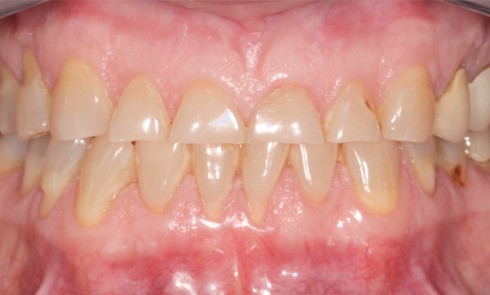

Article réservé à nos abonnés Ma première « three step technique »

Les destructions des tissus dentaires liées à des phénomènes érosifs sont de plus en plus fréquentes et touchent environ 40 %...